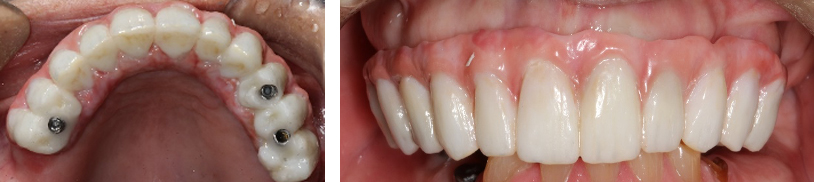

A fixed all-zirconia combination screw- and abutment-retained prosthesis was planned for the mandibular arch. Multiunit abutments were used to correct the angulation of the tilted distal implants54 and were torqued per the manufacturer specifications. Novel retentive abutments that would preclude the need for screws and cements were attached to the four anterior implants, rotated to ensure they were parallel to each other, and torqued per the manufacturer specifications (Figure 24).41

Impression copings were attached to the abutments (Figure 25); an abutment-level impression was made (Figure 26), and records were registered and sent to the laboratory for fabrication of the definitive prosthesis. A CAD/CAM all-zirconia prosthesis was planned (Figure 27, left) and fabricated by the laboratory. The prosthesis would have recesses on its intaglio surface in the location of the four anterior implants to provide space for the pickup of the attachment housings (Figure 27, right).41

The denture attachment housings were placed over the four anterior abutments (Figure 28).41 The prosthesis (Figure 29) was tried and adjusted as needed, and the occlusal vertical dimension was verified.41 Block-out rings were placed around the abutments in the mouth to block out the undercuts below the abutments.41 Attachment pickup material was placed around the four anterior abutments in the mouth and in the recesses of the prosthesis, and the prosthesis was placed in the mouth.41 It was attached posteriorly to the distal-most implants with screws. After the polymerization of the pickup material, the screws of the multiunit abutments were loosened, and the prosthesis was removed from the mouth. The denture attachment housings were picked up in the zirconia prosthesis (Figure 30).41 The black nylon processing inserts present within the attachment housings were removed and replaced with new ones.41 The prosthesis was adjusted, finished, and polished. Then the black inserts were replaced with the retentive inserts.41 The amount of retention can be increased by using inserts that provide an added degree of retention, if needed.41 The prosthesis was placed in the patient's mouth, and the distal screws used to attach the multiunit abutments to the prosthesis were tightened and torqued per the manufacturer's recommendation (Figure 31). The screw-access holes were packed with polytetrafluoroethylene and composite resin.

Fig 24. Multiunit abutments (gold) were attached to the distal-most implants, and novel abutments (pink) (LOCATOR F-Tx, Zest Dental Solutions) were attached to the four anterior implants.

Fig 29. All-zirconia restoration.

Fig 30. The denture attachment housings (pink) were picked up in the prosthesis.

Fig 31. The prosthesis was placed in the patient’s mouth.